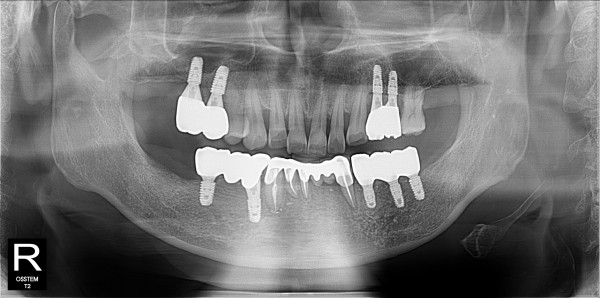

구치부 임플란트 최고관리자 0건 23-11-07 18:31 본문 구치부 임플란트 + 전치부 크라운 목록 이전글구치부 임플란트 23.11.07 다음글구치부 임플란트 23.11.07 댓글목록 0 댓글목록 등록된 댓글이 없습니다.